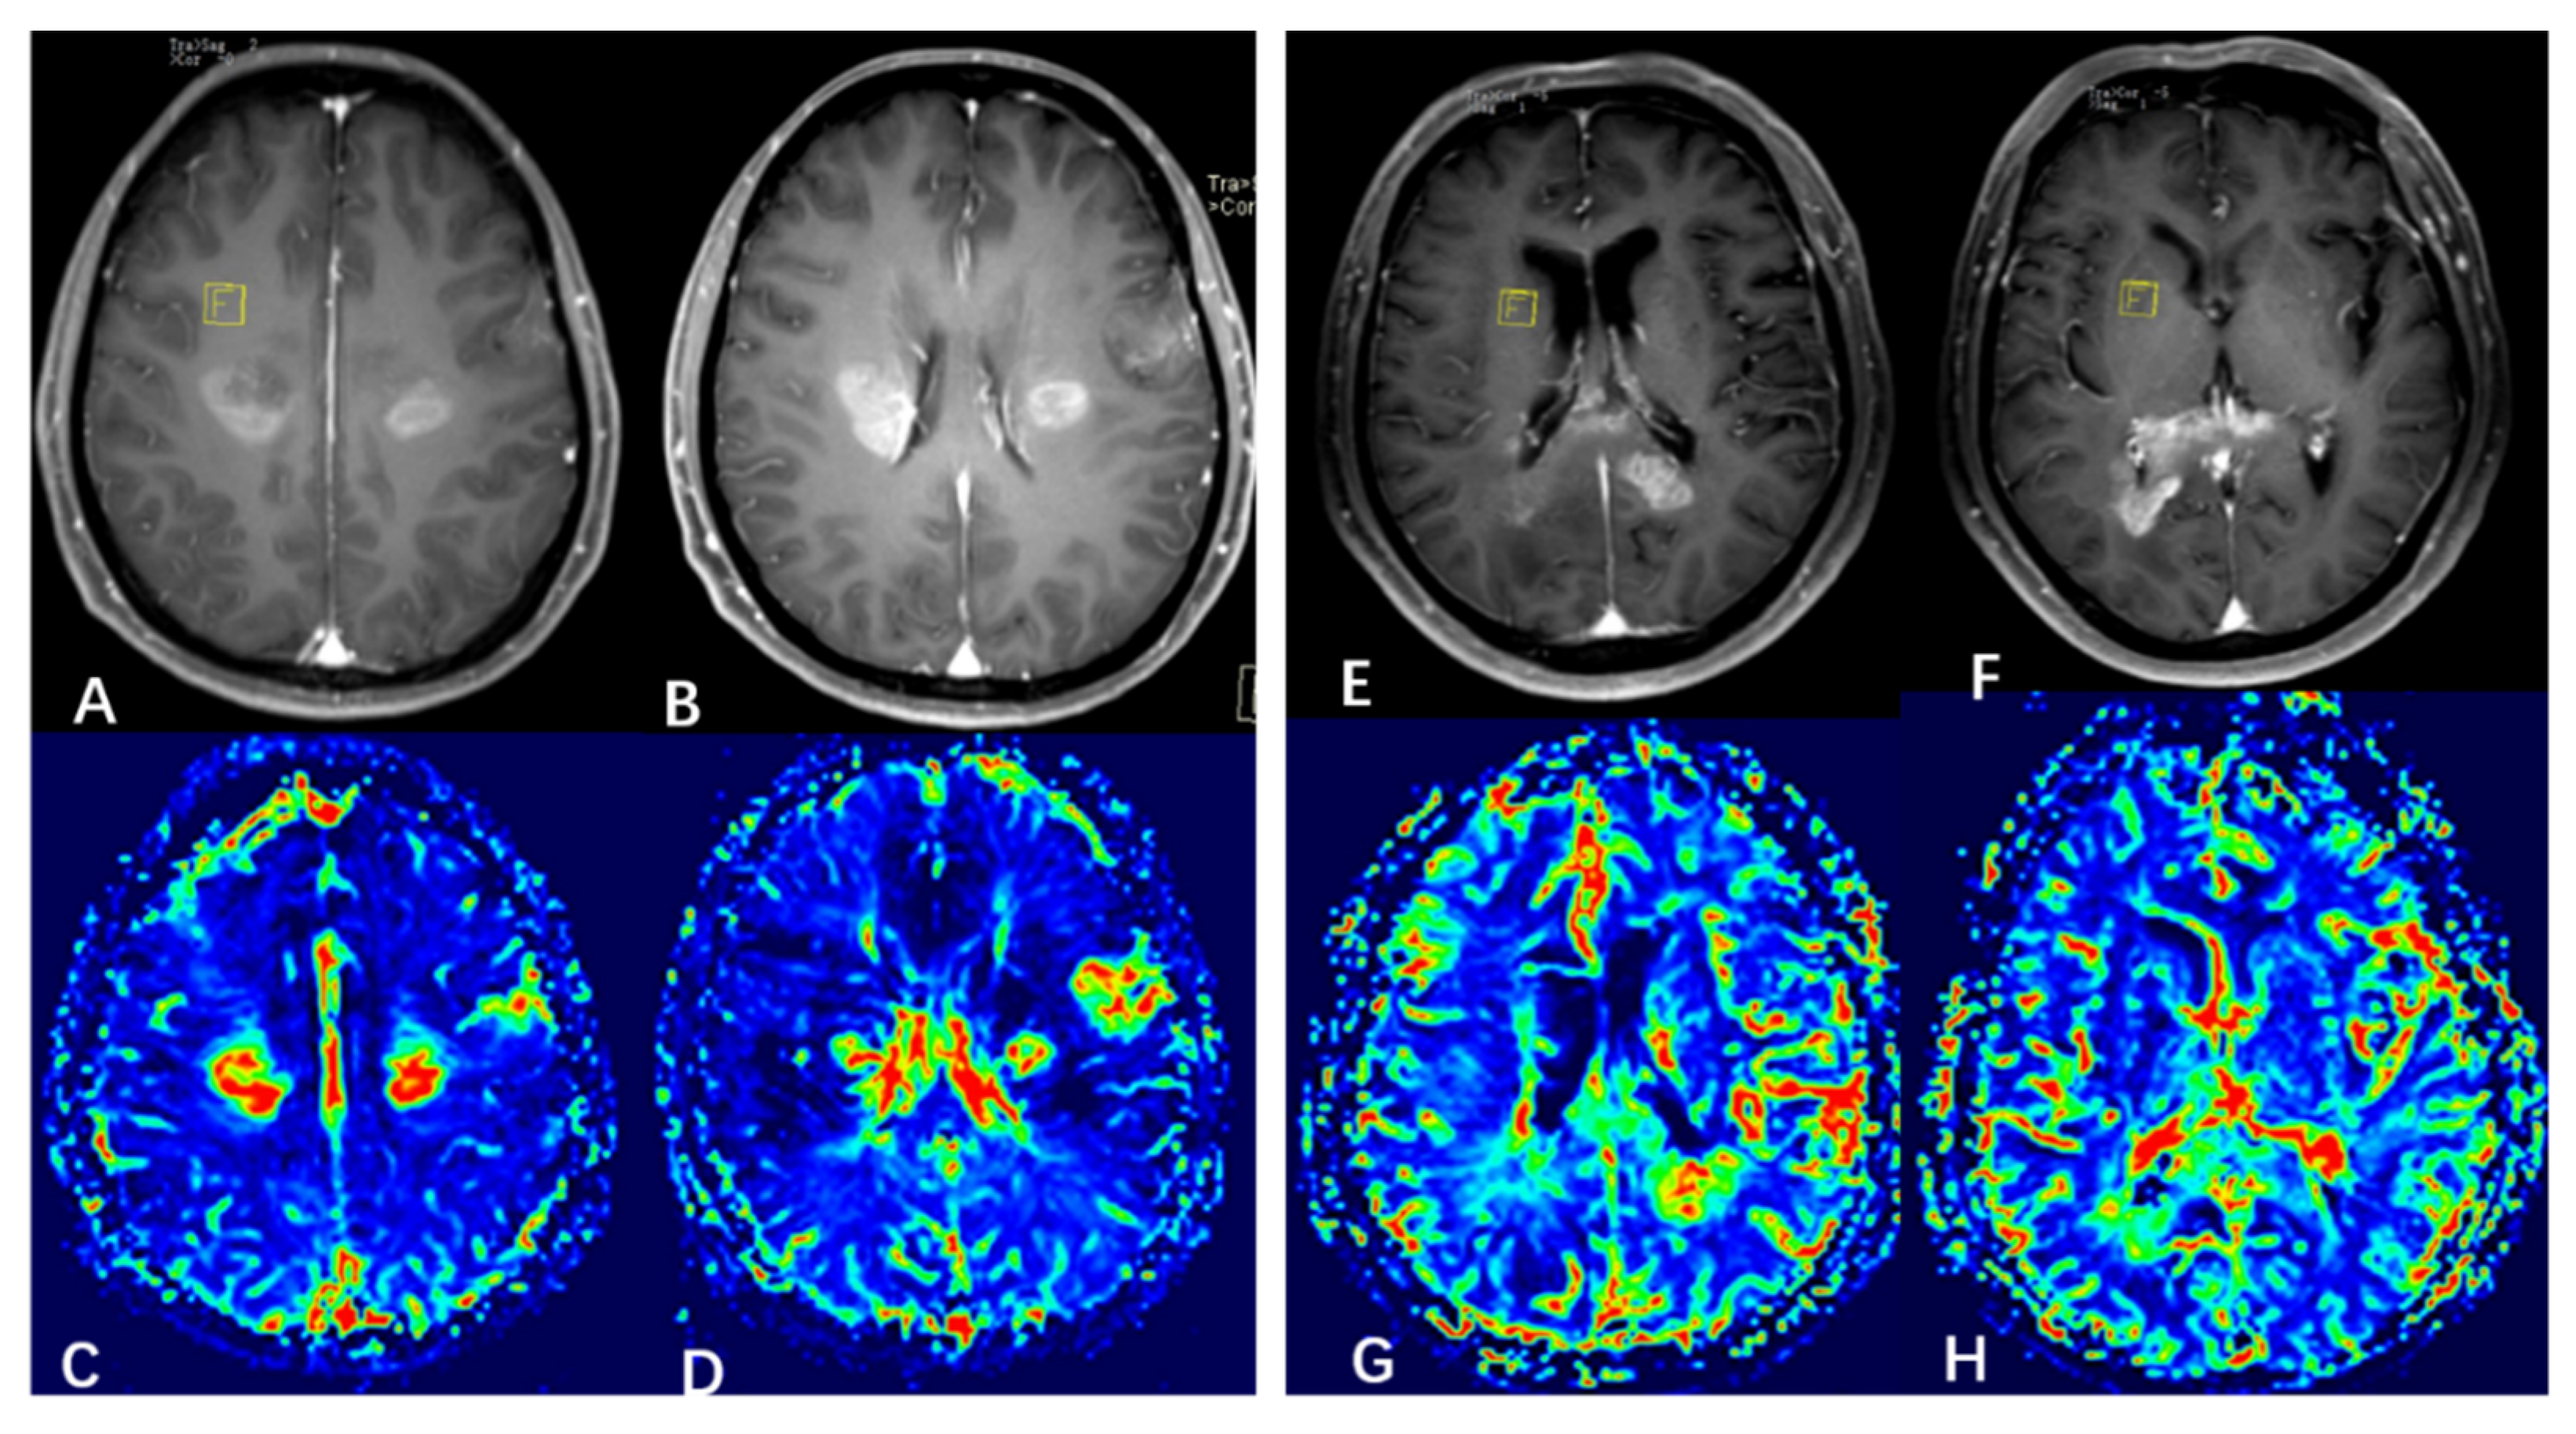

3.2. Probabilistic Fiber Tracking

3.3. Hierarchical Clustering

3.4. Subgroup Differences

| rCBV | 2.31 ± 0.95 | 1.73 ± 0.48 | −3.11 | 0.002 * |